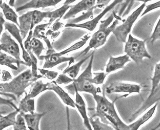

-I060.png)

I060: Renal Glomerulus Endothelial Cells (RGEC)

Renal Glomerulus Endothelium